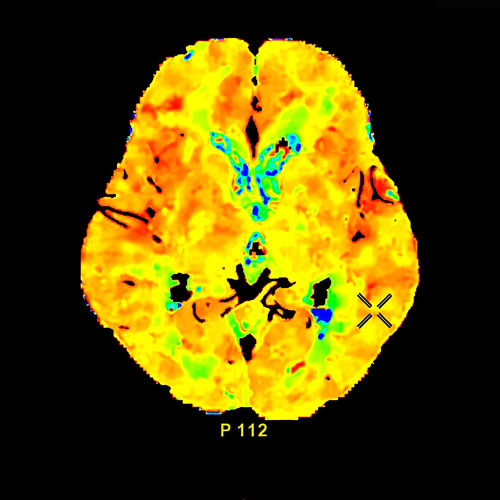

Neuroradiology

Advances in neuroradiology have transformed diagnostic capabilities for injuries and disease of the brain and nervous system. From evaluating concussions to examining images of brain tissue for signs of degenerative disease such as Alzheimer’s or Parkinson’s. We obtain specialized images of the brain including MR Spectroscopy, Dynamic Perfusion Imaging, Diffusion Tensor Imaging and Functional Imaging.